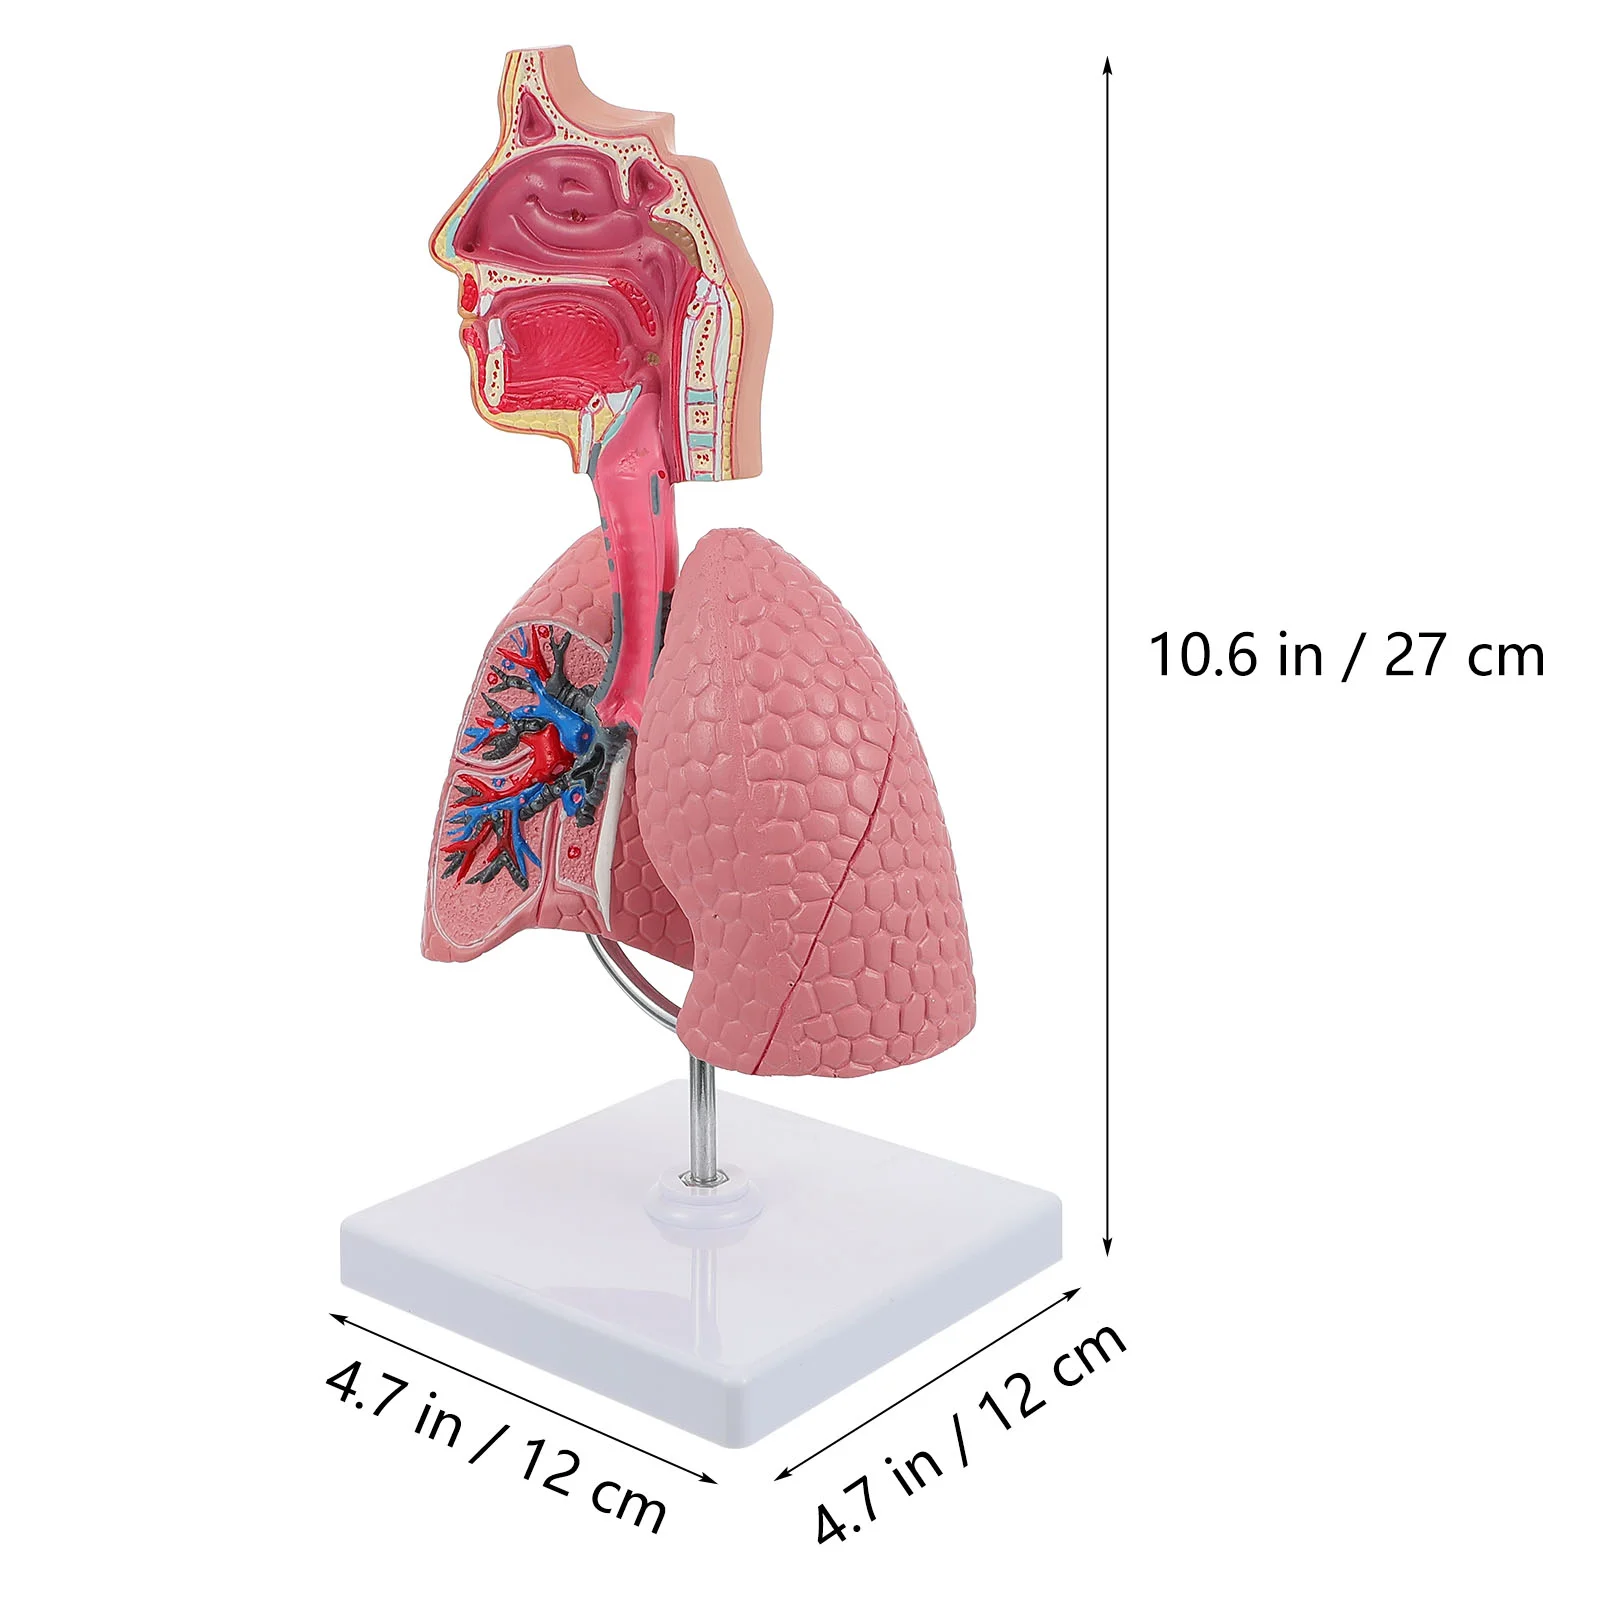

Model Lung Respiratory Teaching System Human Display Tool Anatomy School Lungs Anatomical Heart Educational Nasal Toy Nursing

sku: 1005005188844360

ACCORDING TO OUR RECORDS THIS PRODUCT IS NOT AVAILABLE NOW

$36.74